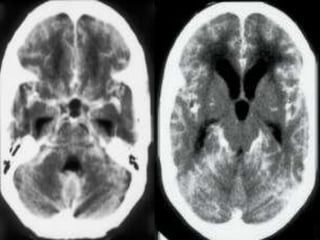

Grey and white matter differentiation

• Normally Grey matter is outer denser

structure and white matter in inner

hypodenser.

• Grey matter contains neurons cell bodies

while white matter contain axons with rich

fatty myelin sheath making it hypodense.

• This differentiation is loss in case of cerebral

odema.

Grey and whitematter differentiation • Normally Grey matter is outer denser structure and white matter in inner hypodenser. • Grey matter contains neurons cell bodies while white matter contain axons with rich fatty myelin sheath making it hypodense. • This differentiation is loss in case of cerebral odema.